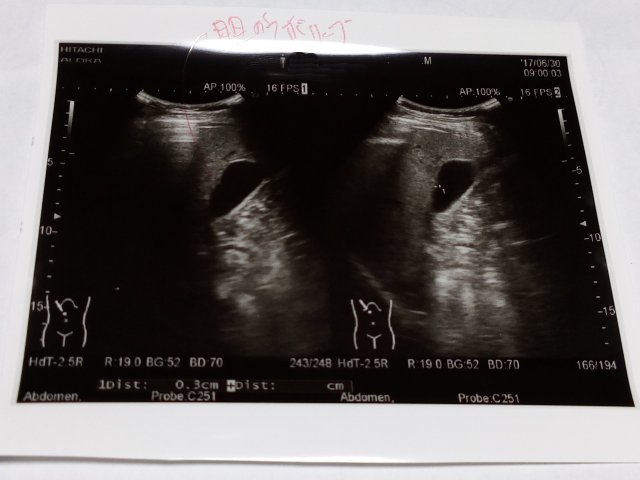

Img_20170701_0114161 胆のうポリープ